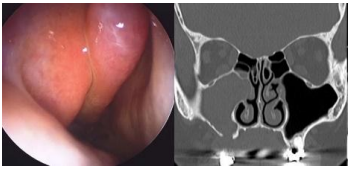

Mulher, 52 anos de idade, apresentou dor dentária há 3 meses. Na ocasião, foi submetida à extração do segundo molar superior direito, com fechamento adequado e cicatrização completa do alvéolo dentário. Desde então, evoluiu com rinorreia purulenta unilateral à direita, cacosmia e sensação de pressão facial ipsilateral. Realizou tratamento com amoxicilina-clavulanato por 14 dias, sem melhora clínica. A endoscopia nasal à direita e a tomografia de seios da face sem contraste demonstraram as imagens apresentadas a seguir:

Enunciado 4540963-1

Com base nesse quadro, qual a melhor conduta a ser adotada?